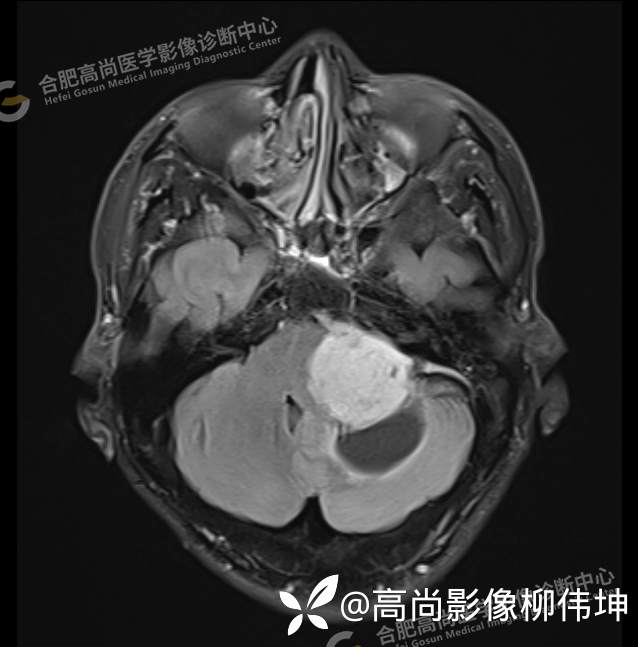

T1WI-tra

颅脑MRI平扫+增强示:双侧大脑半球对称,左侧桥小脑角区可见一团块状异常信号影,边界尚清,病灶与小脑幕宽基底附着呈“D”字征,上缘指状伸入幕缘上生长,病灶大小约43mmx42mmx36mm,其内信号不均,T1WI呈等低信号,T2WI呈混杂等高信号;FLAIR呈高信号,内可见条状低信号影,DWI呈稍高信号,ADC呈低信号,弥散轻度受限,病灶后方左侧小脑半球区可见一大小约33mmx16mm的弧形长T1长T2信号影,FLAIR呈低信号,其周围可见片状高信号影,相邻桥小脑角增宽。脑桥、小脑蚓部,小脑半球、第四脑室、环池受压变形,向右侧偏移,四脑室明显变窄,增强扫描病灶可见不均匀明显强化,邻近脑膜可见线样强化改变。其后方囊性灶未见异常强化。邻近骨质未见明显异常信号。左侧内听道显示正常;左侧中耳乳突内可见不规则性长T1长T2信号影。余脑实质内未见局灶性信号异常。双侧侧脑室及第三脑室体积增大,中线结构居中。矢状面示垂体形态大小正常,未见局灶性异常信号。

1.左侧桥小脑角区占位伴周围囊变,轻度梗阻性脑积水;考虑左小脑幕脑膜瘤。